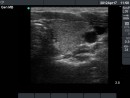

Follow-up examinations (rows from 1st to 8th):

1. The patient initially presented with a large thyroid, therefore we suggested definitive therapy.

2. Note the relation between volume, echogenicity, vascularization and hormone levels.